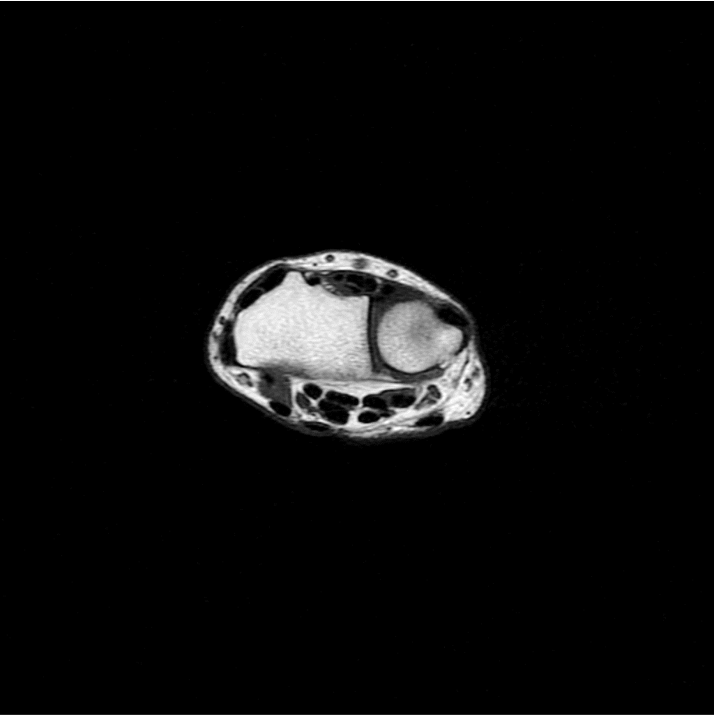

1:29 min촬영속도의 혁신, IAI

기존

IAI

IAI는 AI Deep learning을 통해 기존 장비의 촬영 프로토콜을 최적화합니다.

기존 프로토콜 대비 촬영 시간을 50% 단축시키며, 이미지 퀄리티는 증가합니다.